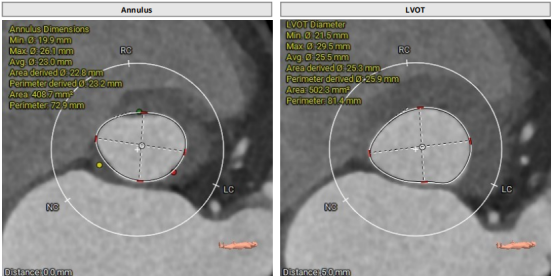

CT結(jié)構(gòu)評估

患者為功能性二葉瓣,瓣葉增厚,輕度鈣化,鈣化主要集中在左竇瓣葉上,左冠脈高度較低,結(jié)合瓣葉長度,竇部結(jié)構(gòu)綜合評估左冠風(fēng)險較低,但左冠瓣葉瓣尖處有鈣化團塊,在球擴以及瓣膜釋放時仍需注意左冠灌注情況,由于鈣化團塊位置特殊,建議做冠脈保護處理,右側(cè)股動脈作為主入路,穿刺點位于股骨頭中段即可。

采取局麻+鎮(zhèn)靜麻醉方式,避免氣管插管對循環(huán)打擊;預(yù)裝VenusA L26瓣膜,患者心功能較差不進行球囊預(yù)擴張,直接放瓣膜;升主動脈稍寬,注意器械通過,必要時snare輔助;建議行左冠保護;右股動脈作為主入路。